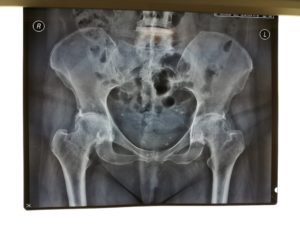

Περίπτωση ταυτόχρονης αρθροπλαστικής AMIS για αμφοτερόπλευρη οστεοαρθρίτιδα Ισχίου

Η ασθενής είναι 56 ετών και υπέφερε από οστεοαρθρίτιδα και των δύο ισχίων με έντονο πόνο και σοβαρή δυσκολία στη βάδιση.

Η καλή κατάσταση γενικής υγείας επέτρεψε να γίνει ταυτόχρονη, σε μια επέμβαση, αρθροπλαστική Ισχίου.

Ο ατραυματικός και συγκριτικά αναίμακτος χαρακτήρας της AMIS είχε ως αποτέλεσμα την άμεση κινητοποίηση της ασθενούς. Λίγες ώρες μετά την επέμβαση ταυτόχρονης AMIS η ασθενής βάδισε με τη βοήθεια περιπατητήρα.

Την επόμενη μέρα βαδίζει αυτόνομα και πρακτικά είναι έτοιμη να επιστρέψει σπίτι της.

Δύο εβδομάδες μετά την επέμβαση η ασθενής είναι πολύ ευχαριστημένη, κινείται αυτόνομα και είναι ιδιαίτερα ικανοποιημένη από το γεγονός ότι δε θα χρειαστεί να επιστρέψει στο χειρουργείο για μια δεύτερη επέμβαση για την αρθρίτιδα που την ταλαιπωρούσε.